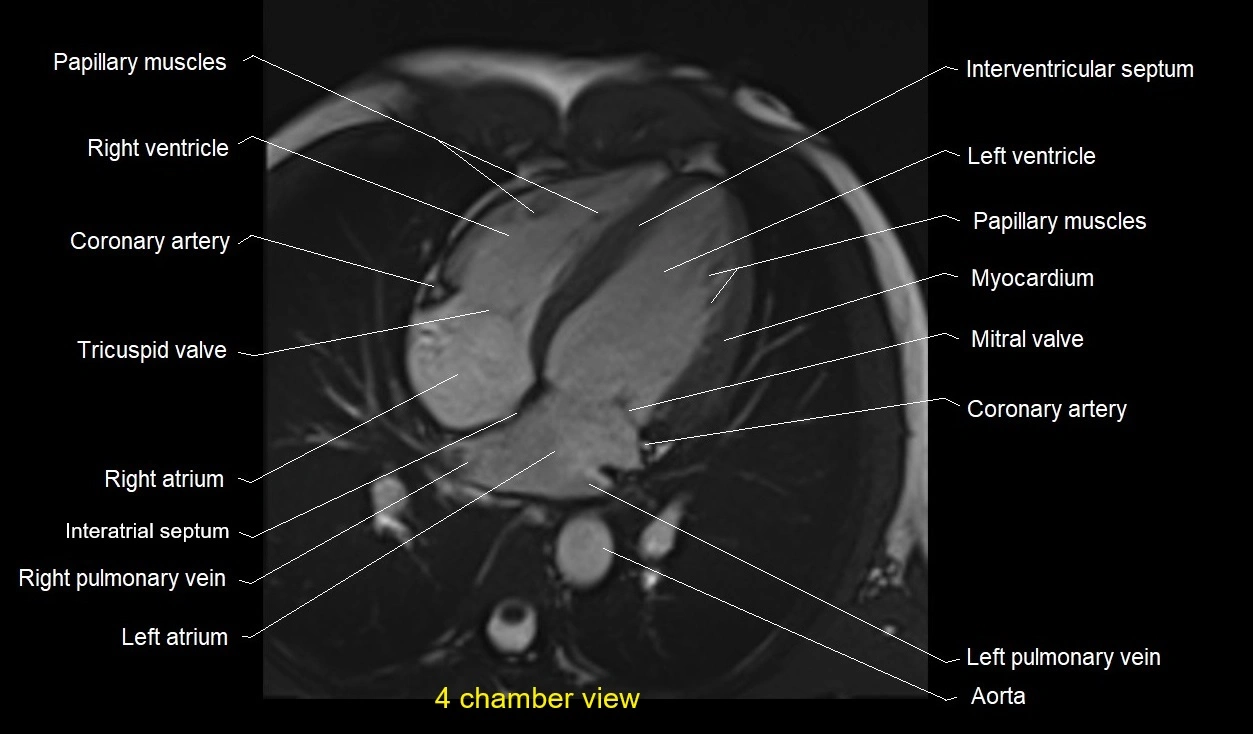

MRI image